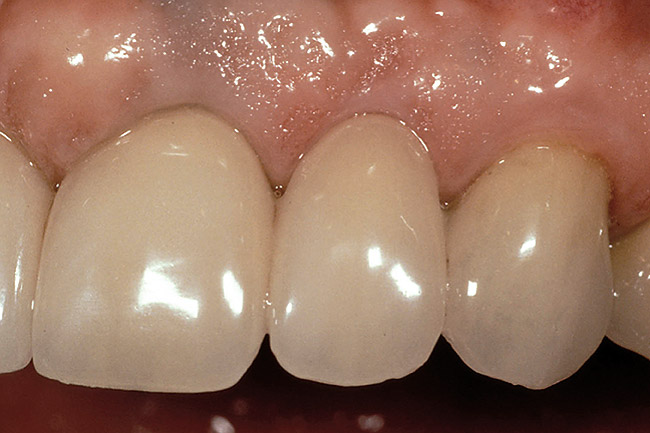

Figure 2  Note the invisibility of the marginal line in the completed veneers, even though the margin has not been carried below tissue.

Figure 2

A clinician is faced with 3 options for for margin placement when considering an anterior esthetic restoration: supragingival, equigingival (ie, even with tissue), and subgingival.1 The supragingival or equigingival margin will have the least impact on the periodontium and, classically, was only used in nonesthetic areas because of the stark contrast in color and opacity of traditional restorative materials. With the advent of adhesive dentistry, resin cements, and more translucent restorative materials, the ability to place supragingival or equigingival margins even in esthetic areas is now a reality (Figure 1 and Figure 2). The primary requirement of a material to enable its use in esthetic areas supra- or equigingivally is a high level of cervical translucence. Materials such as feldspathic porcelain, as well as pressable ceramics, meet this requirement. Consequently, whenever possible, these restorations should be chosen not just for their esthetic advantages, but for their favorable periodontal impact as well. The greatest biologic risk occurs when placing subgingival margins.2